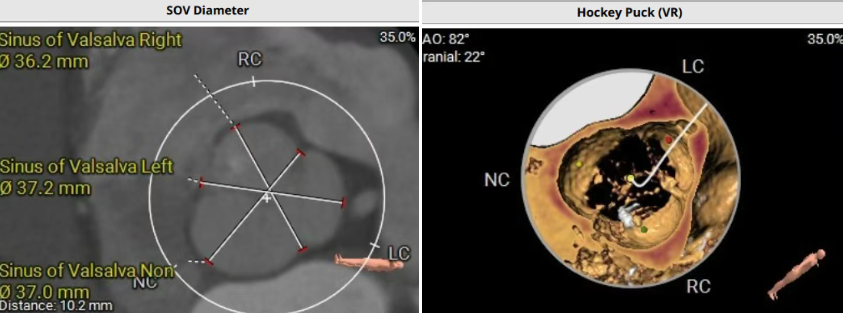

術前CT評估提示,患者主動脈瓣三葉瓣,瓣葉增厚,舒張期右冠瓣脫垂,右冠瓣瓣葉輕度鈣化,存在三個瓣竇,分布較均勻;主動脈瓣環周長折算直徑28.0mm;左心室流出道周長折算直徑29.5mm,無鈣化,無狹窄;STJ直徑35.3mm,升主動脈直徑41.8mm;雙側冠脈開口高度可LCA13.5mm ,瓣葉長17.2mm;RCA33.9mm,瓣葉長10.0mm;側左冠脈輕度鈣化;橫位心,左室主動脈夾角為135°;